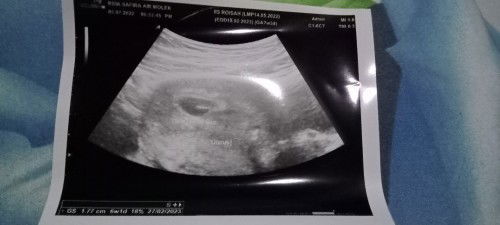

Tadi usg ke dua.. tapi mundur 1 mggu lbih dari hpht 🥺🥺 takut kenapa2... Penantian 7thn dan punya riwayat keguguran Hpht 7w3d Usg 6week 1day